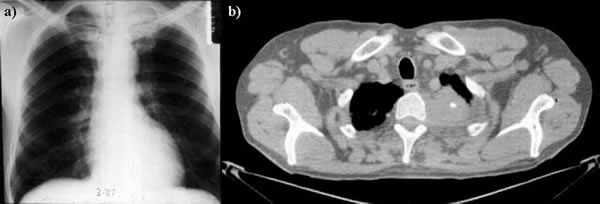

The subclavian artery can usually be dissected through the subadventitial plane (Video 8). Local branches (e.g., the internal mammary artery, thyrocervical trunk, or occasionally the vertebral artery) should be identified and transected if necessary. If the subclavian artery is invaded by tumor (Figure 10), the involved segment can also be resected and reconstructed through a posterior approach (Figure 11). After systemic heparinization, the artery is cross-clamped proximally and distally excluding the invaded segment and revascularized using either an end-to-end anastomosis or, more commonly, the interposition of a polytetrafluoroethylene (PTFE) graft, 6 to 8 mm in diameter (Video 9).

| Figure 10. Chest CT-scan shows the invasion of the subclavian artery by Pancoast tumor. | Figure 11. The invaded artery was resected and replaced by a PTFE graft through a posterior approach. |